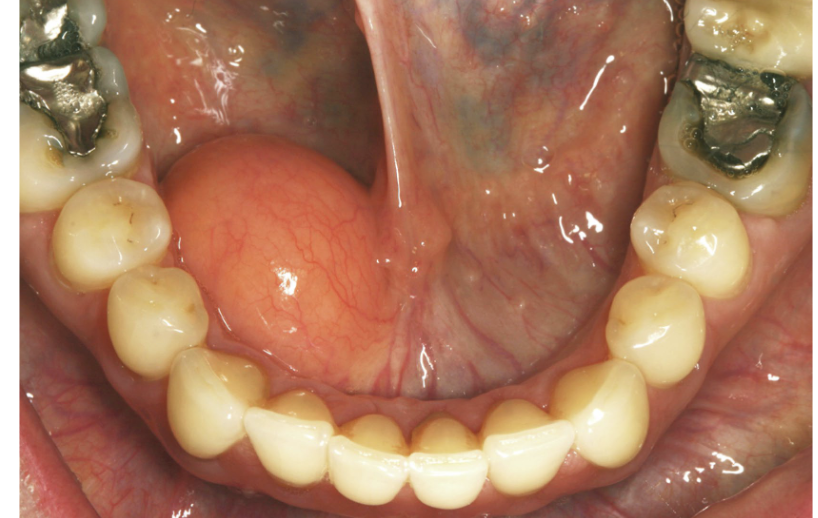

Clinical presentation:

Pink/red macule to blue/purple mass

Presentation can vary based on vasculature involved

Multiple, Blue / purple macules, plaques and nodules on face and oral mucosa

Kaposi Sarcoma

Most common locations to see Kaposi Sarcoma

Hard palate, gingiva, tongue.